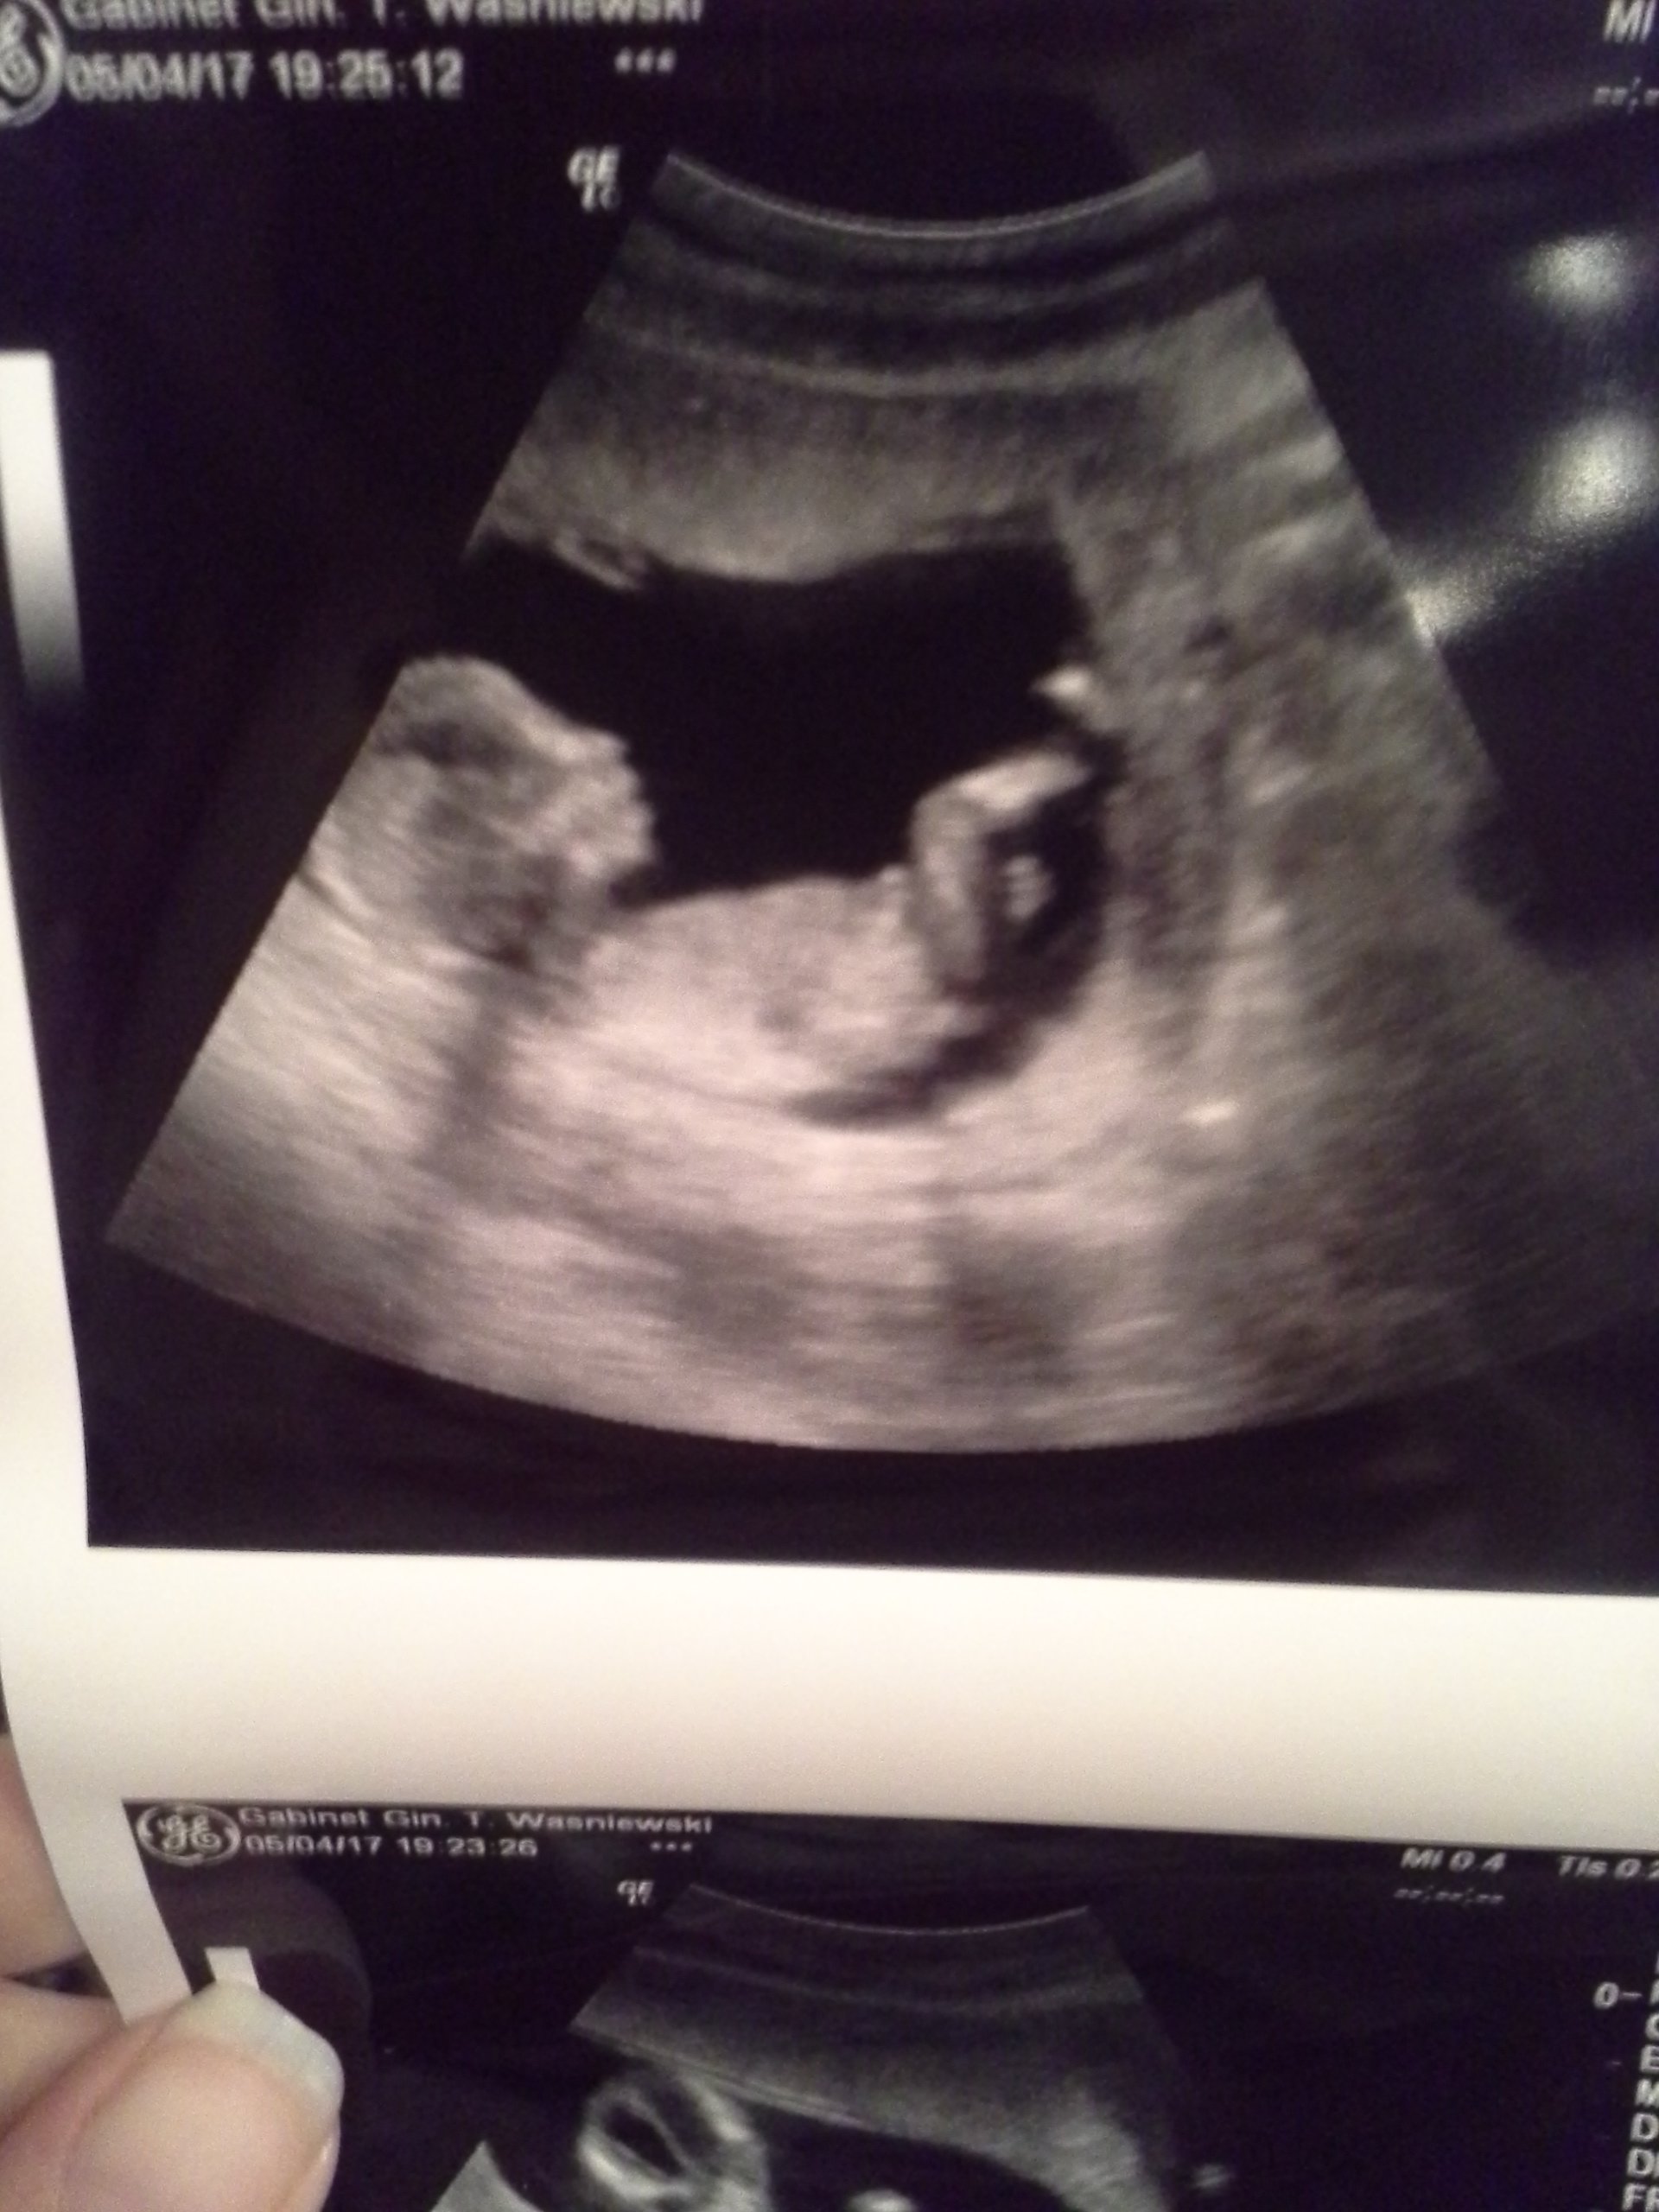

W końcu jestem po wizycie. Z Małą wszystko dobrze. Ma już 8,5cm. :)

Lekarz mówił, że bóle brzucha, kłucia itp. są normalne na tym etapie ciąży. Jak macica cała "wyjdzie" na zewnątrz to kłucia zamienią się w ciągnięcie w pachwinach. Jeżeli złapie mnie ból niedowytrzymania to wtedy mam wziąć nospę, jeżeli po nospie nie przejdzie, lub zacznę plamić to wtedy mam do niego dzwonić.

Normalnie kamień spadł mi z serca.

Oto moja córeczka :D

Rany jaka śliczna! Bardzo fotogeniczna :) Gratuluję! Rzadko które zdjęcia tak wyraźnie wychodzą. Jak sobie fajnie leży tak wygodnie podparta :)